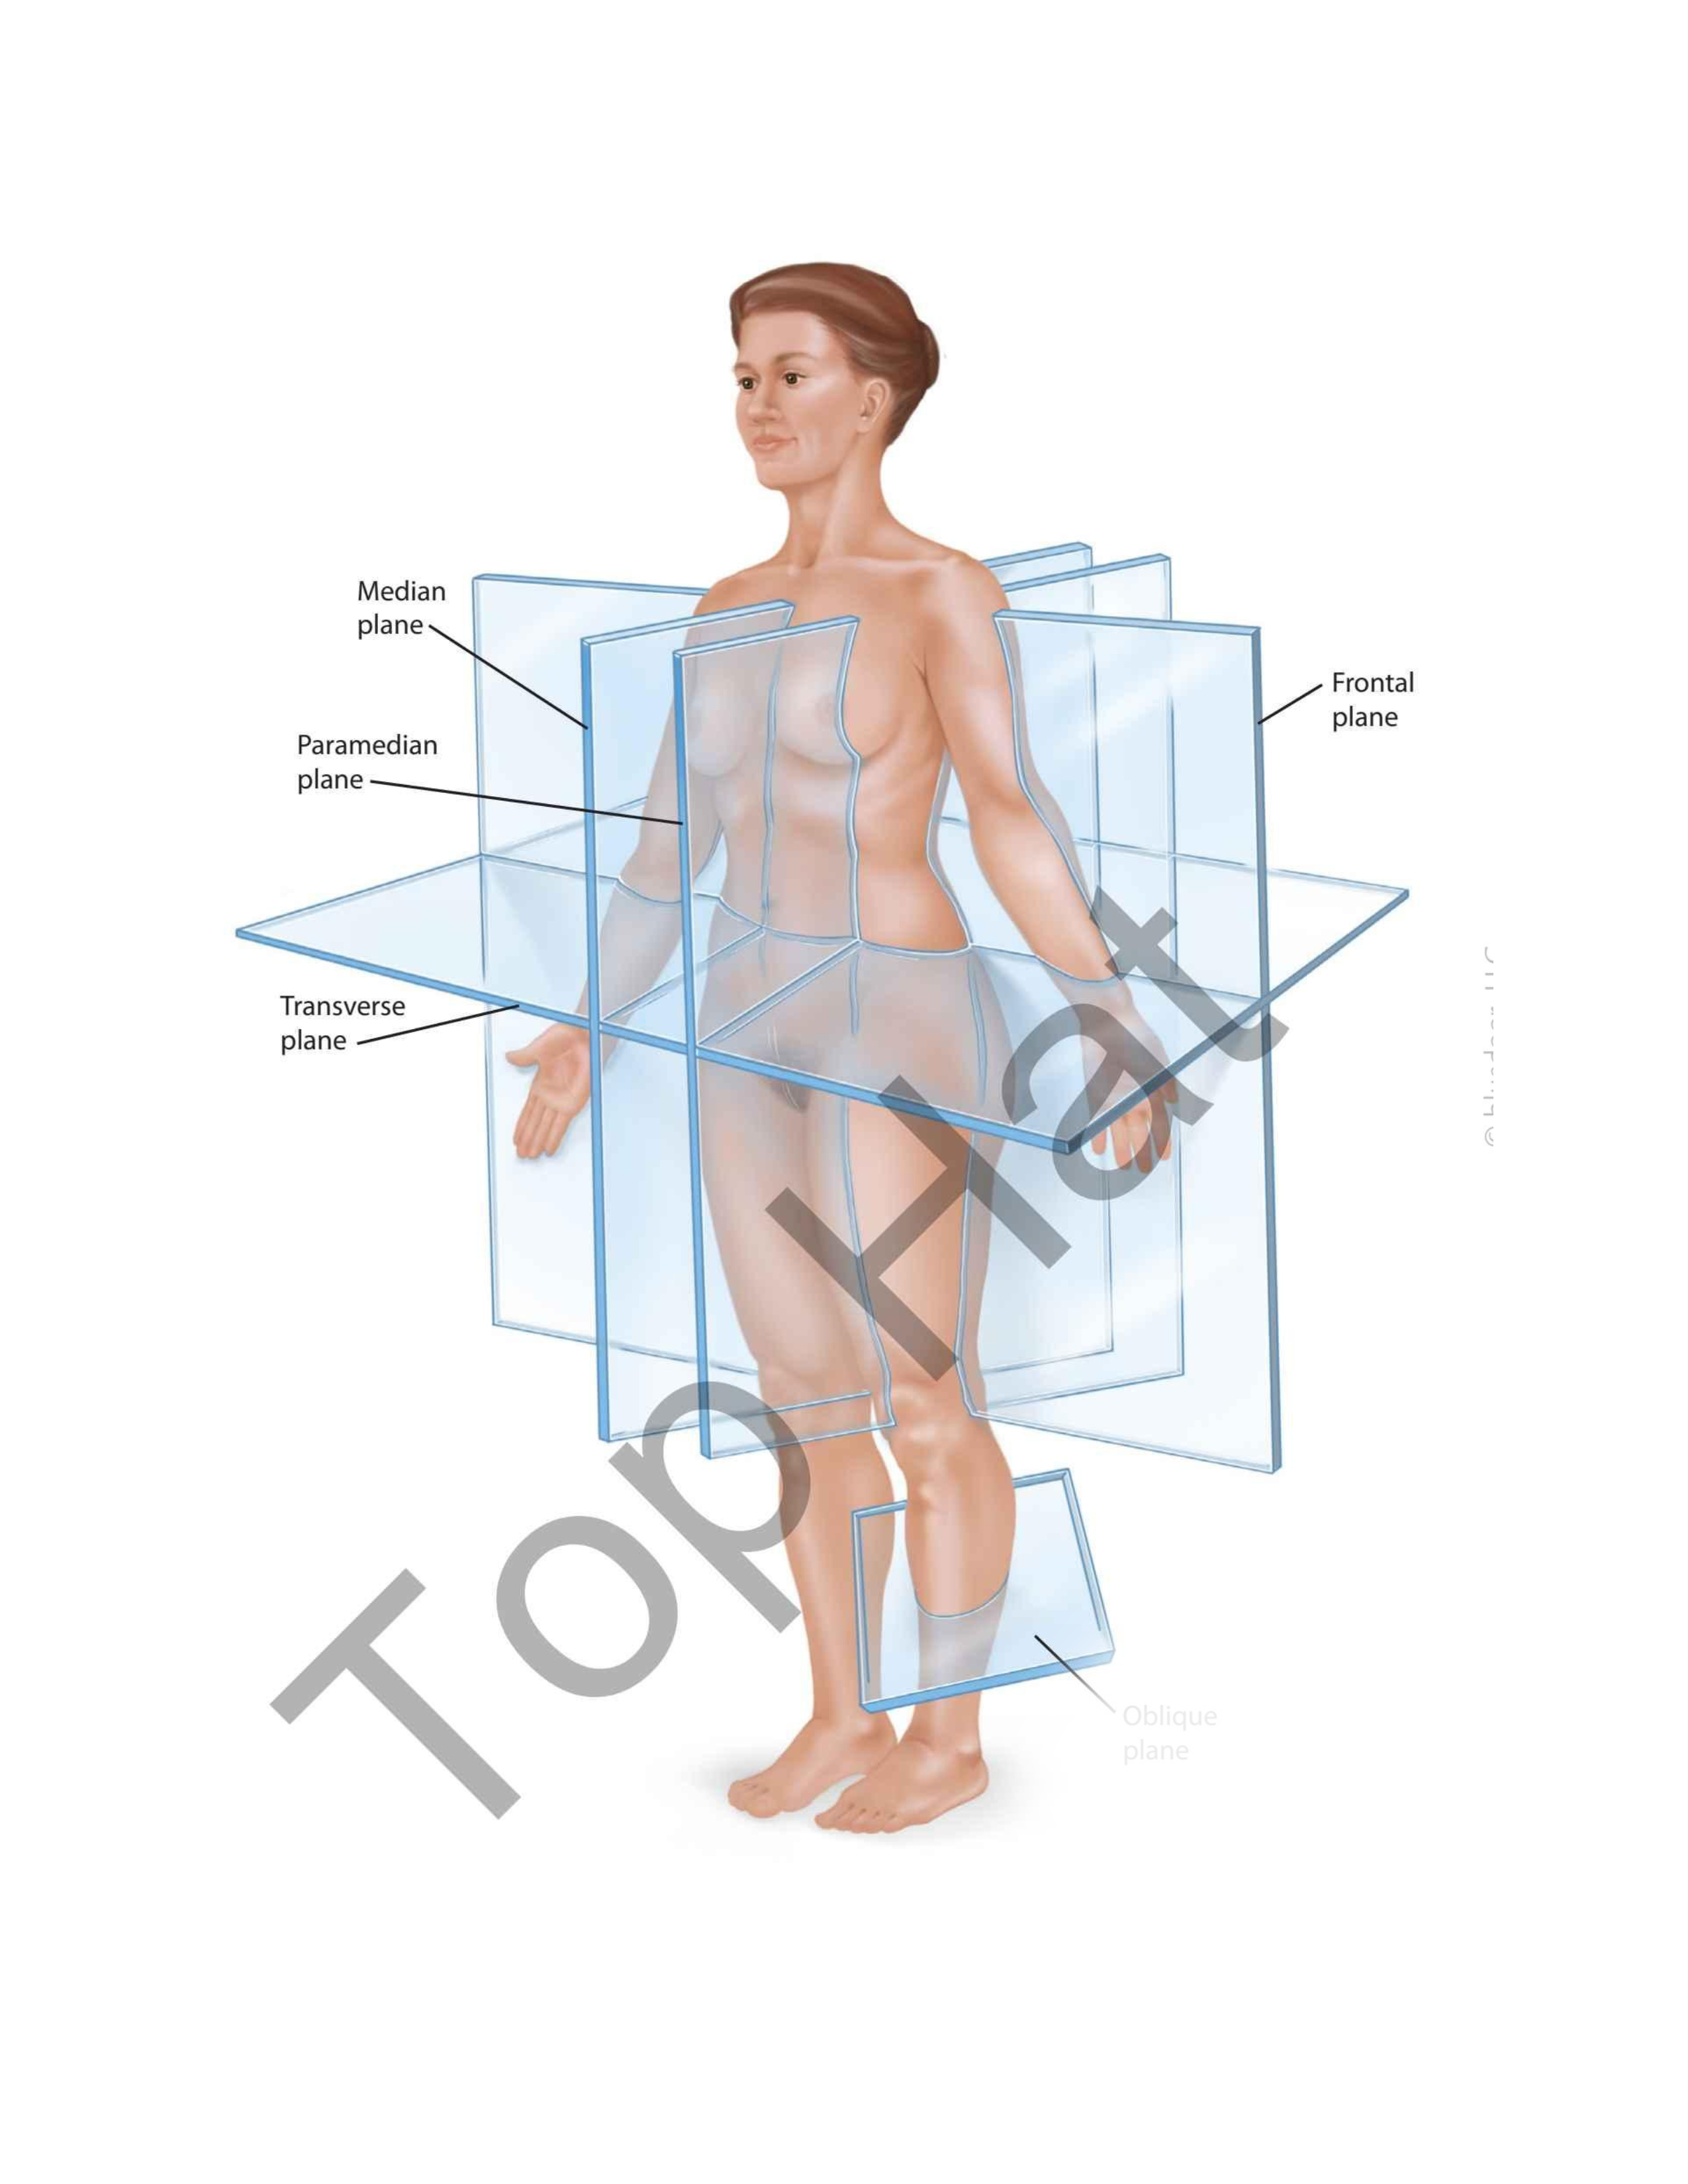

Median Plane

Frontal Plane

Oblique Plane

Transverse Plane

Paramedian Plane